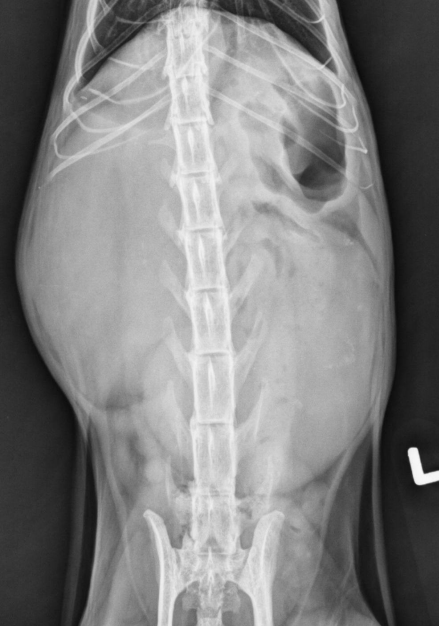

●10 yo female sterilized rottweiler

●Vomiting after every meal for 2 days

● Soft tissue opacity in the area of stomach

● Metal staple in colon

● Metal implant in one knee (from

previous surgery)

● Soft foreign body in stomach – grass,

fabric, wrapping paper

major organs in abdo cavity are hazy and poorly viewed, and lumen of stomach not viewable due to fabric foreign body in stomach.

cecum visible on VD, gas filled bubbles.